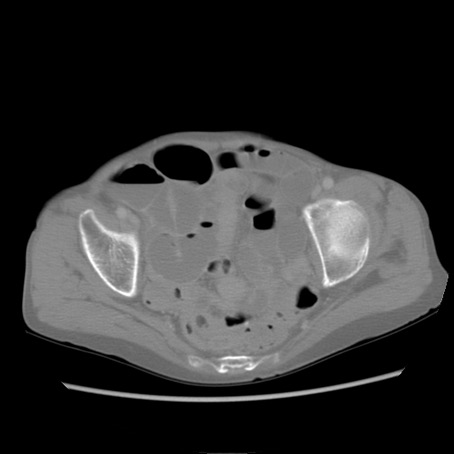

冠状断像

【症例】80歳代女性

【主訴】胸のつかえ感

【現病歴】約9時間前に食後から胸のつかえた感じあり、嘔吐あり、来院。

【既往歴】胃癌(全摘)、胆摘、虫垂炎

【身体所見】心窩部に圧痛あり、反跳痛なし。

【データ】WBC 5700、CRP 0.05